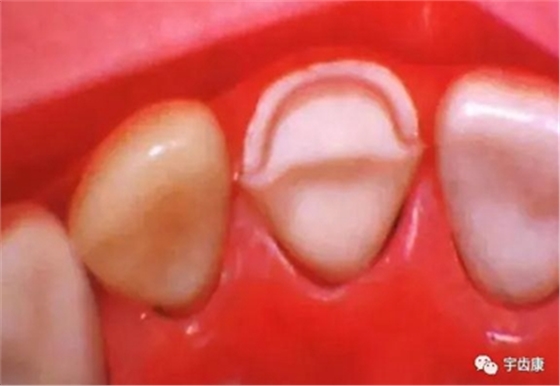

4. 預(yù)留修復(fù)體的空間

5. 邊緣的適合性

牙體各個面的解剖厚度

烤瓷牙結(jié)構(gòu)知識

烤瓷牙的設(shè)計方式